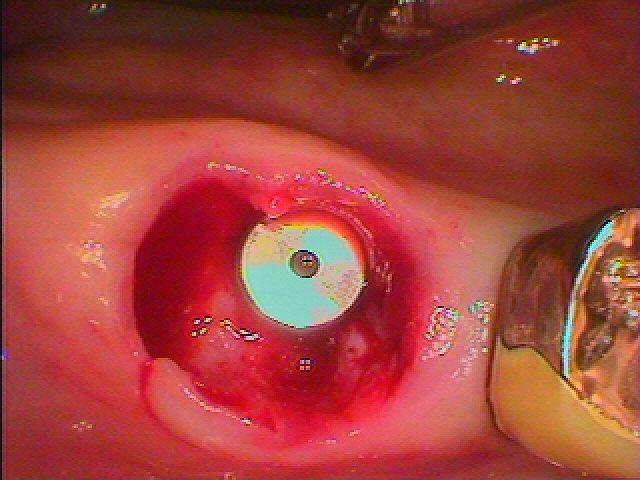

このように5㎜の13㎜というインプラントを埋入しています

隙間には像骨処置として骨補填材を敷き詰めています

このように埋入しています

しっかりとしたインプラントが埋入できました